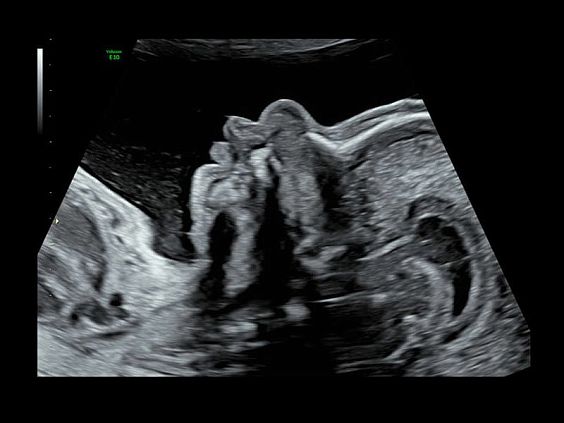

• Программа 3D и режим инверсии (при наличии специализированных датчиков)

• Advanced 4D - расширенный пакет 4D для механических объемных датчиков RM6C, RIC5-9, RIC6-12, RSP6-16:

• Режим 4D - трехмерное сканирование в реальном масштабе времени

• Томографический ультразвук (TUI)

• Объемное контрастирование прямой плоскости - Basic VCI (VCI-A + VCI static)

• Активирует SonoRenderLive в 4D

• E4D advanced - расширенный пакет электронного 4D ультразвука (e4D) для электронного объемного датчика eM6C:

• Режим 4D - трехмерное сканирование в реальном масштабе времени с ультравысокой частотой кадров

• Режим бипланового сканирования Bi-Plane в В-режиме и ЦДК.

• Электронный STIC - eSTIC

• Объемное контрастирование плоскости сканирования VCI-A

• Advanced VCI (Volume Contrast Imaging) - расширенный программный пакет объемного контрастного изображения (VCI) для механических и электронных объемных датчиков:

• Проведение любой произвольной плоскости в 3D/4D (OmniView)

• Объемное контрастирование любой произвольной плоскости (OmniView+VCI)

• Регулировка толщины и формы коронарного среза в 3D/4D (получение коронарной плоскости в 3D/4D, например, для оценки мозолистого тела - автоматическая функция "Corpus Callosum"

• Advanced STIC - расширенный программный пакет для исследования сердца плода в режиме 4D для механических и электронных объемных датчиков:

• Использование цветного, энергетического допплера, В Flow - режим STIC.

• Сочетание с М-режимом - STIC-M-Mode

• Перемещаемый источник света - STICflow

• SonoVCADHeart - программное обеспечение для исследования сердца плода в режиме 3D/4D (быстрый доступ к плоскостям сканирования) по рекомендациям ISUOG